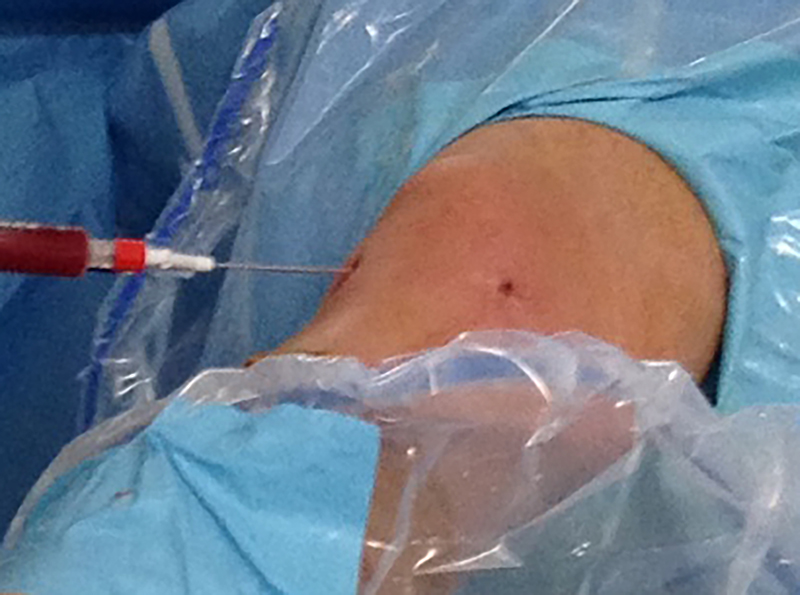

Terminada la reparación artroscópica (fig. 3) se elimina el líquido de la articulación y se procede a inyectar el PRP (fig. 4). Luego de esto se cierran los portales y dejamos al paciente con una férula con rango limitado (de 0 a 90 grados) para proteger la sutura en su fase inicial.

Figura 4: Administración intraarticular del preparado de PRP.